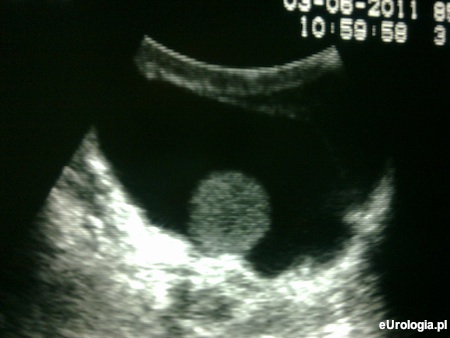

Fot. Obraz USG pourazowego wodniaka jądra.

Powstanie wodniaka jądra może być wynikiem przebytego urazu lub zapalenia. Aby ocenić wielkość i echostrukturę obu jąder warto wykonać badanie USG moszny. Badanie USG jednoznacznie da odpowiedź na pytanie jaka jest wielkość jąder i czy rzeczywiście różnią się istotnie. Bardzo prawdopodobne, że po urazie doszło do zmian zanikowych, które są przyczyną opisywanych objawów. Tak jak każdy mężczyzna powinien Pan samodzielnie palpacyjnie badać sobie jądra czy nie dochodzi w nich do podejrzanych zmian. Więcej informacji na temat samobadania jąder można znaleźć w filmie: Samobadanie jąder - okresowa kontrola moszny.